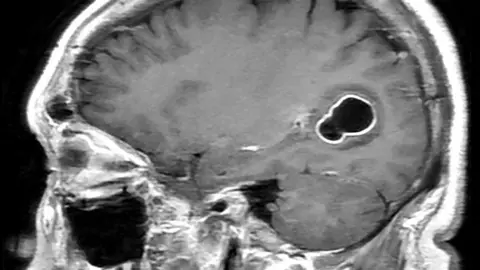

Scans found tapeworm larval cysts in his brain - which cause cysticercosis.

Cysticercosis is a type of infection caused by the larvae of the parasite Taenia solium (T.solium), also known as pork tapeworm, which can lead to cysts (cysticerci) developing in the brain.

According to the US Centres for Disease Control and Prevention (CDC), tapeworm larvae "get into tissues such as muscle and brain, and form cysts. When cysts are found in the brain, the condition is called neurocysticercosis".